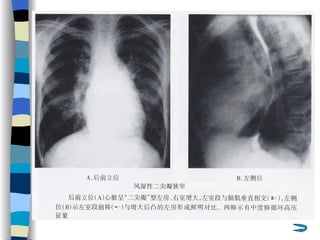

Radiological findings   “ Mitral valve heart ” Marked enlargement of LA Enlargement of RV Dilatation of PA Pulmonary congestion Interstitial edema  (manifested as Kerley B lines)